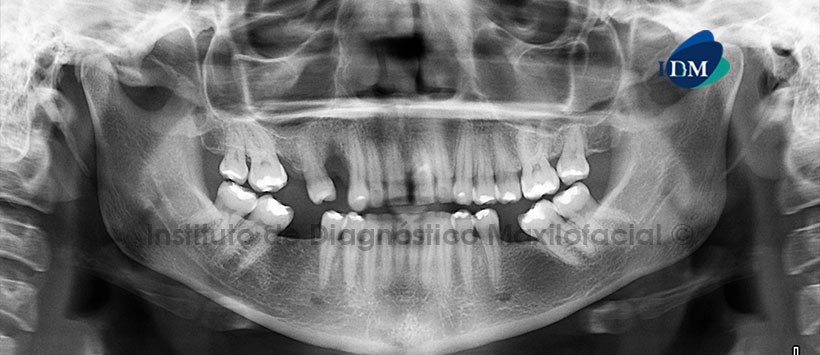

- A la evaluación de la radiografía Panorámica (Figura 1) se evidencia un defecto óseo alveolar localizado en la pieza 21, bifurcación bilateral del conducto dentario inferior y la presencia de múltiples restauraciones coronarias. A la evaluación de la tomografía volumétrica (CBCT) mediante reconstrucción Panorámica localizada (Figura 2), cortes axiales, coronales, sagitales (Figura 3) y transaxiales (Figura 4), se encontró en la pieza 21 una restauración cérvico-vestibular, alteración en la morfología dentaria, caracterizada por la presencia de un surco que se extiende desde la superficie palatina coronaria hasta el segmento apical, compatible con Sindesmo Corono-radicular. Ensanchamiento del espacio periodontal y severo defecto óseo que compromete las superficies vestibular, mesial, distal y palatino.